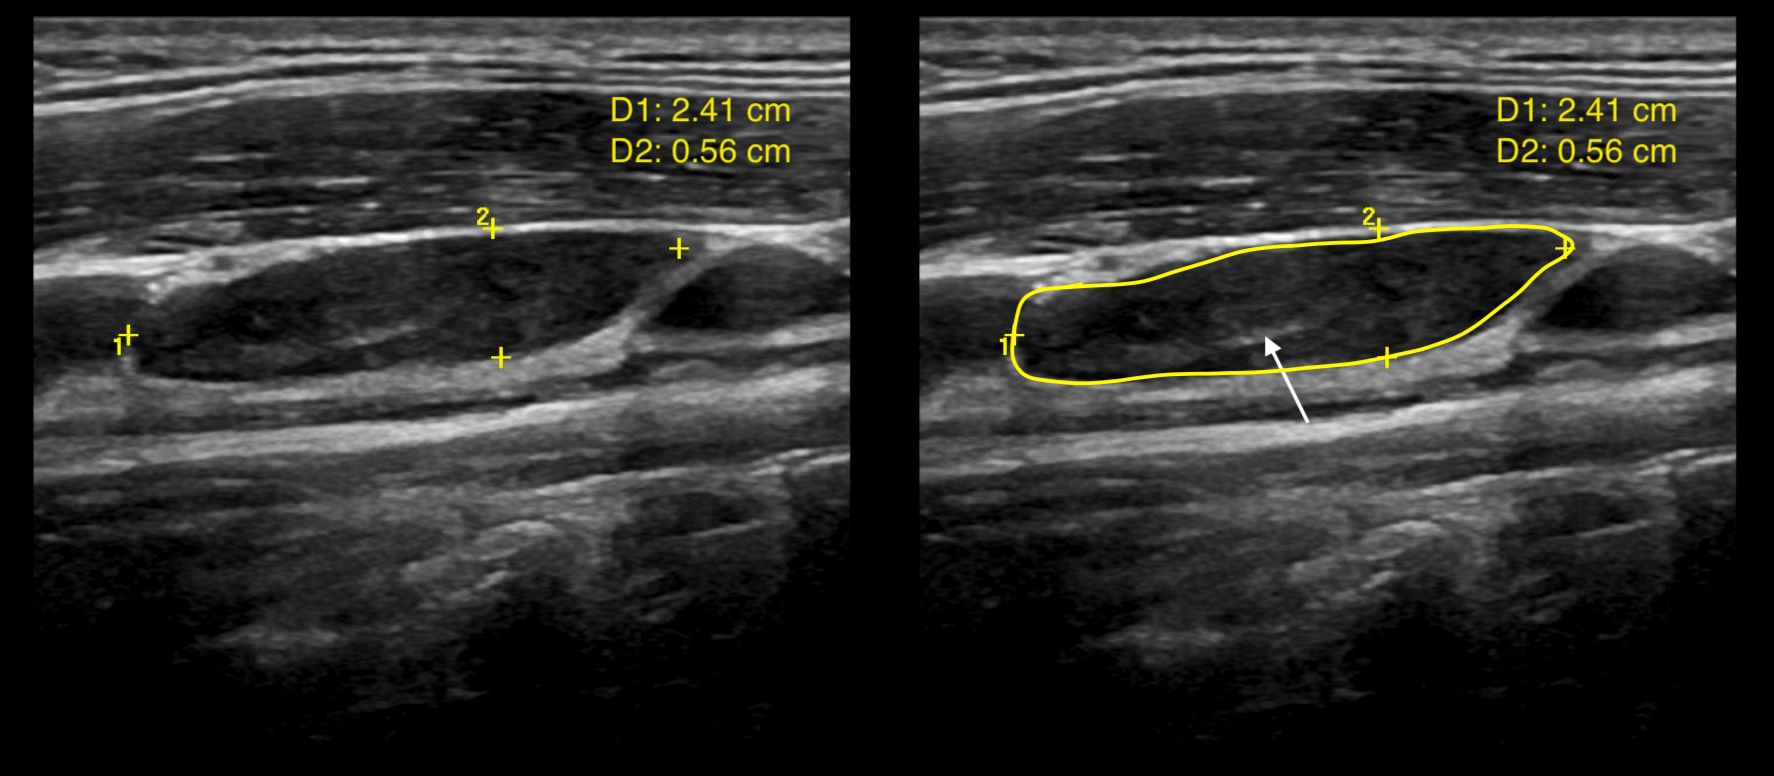

Pseudonodular appearance of Hashimoto’s thyroiditis on ultrasound r Radiology Hashimoto's Thyroiditis hashimoto’s thyroiditis (ht), also known as chronic lymphocytic thyroiditis (clt) or autoimmune thyroiditis. This autoimmune disease of the thyroid gland is the most common. a micronodular pattern on ultrasound is highly diagnostic of hashimoto thyroiditis with a positive predictive value of 95% [ 2 ]. The purpose of this article is to analyze the sonographic appearance of nodular. Radiology Hashimoto's Thyroiditis.